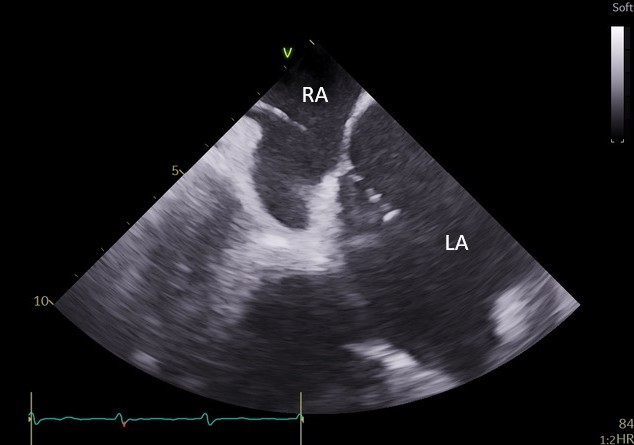

Specjaliści z Pracowni Kardiologii Inwazyjnej I Kliniki Kardiologii UCK przeprowadzili 3 zabiegi zamknięcia uszka lewego przedsionka (ang. LAAO – left atrial appendage occlusion) z wykorzystaniem systemu echokardiografii wewnątrzsercowej (ang. ICE – intracardiac echocardiography).

– U części pacjentów kwalifikowanych do LAAO ryzyko związane z wykorzystaniem obrazowania metodą TEE jest zbyt wysokie ze względu na poważne zmiany chorobowe przełyku. To dotychczas uniemożliwiało wykonanie zabiegu. Obrazowanie metodą ICE pozwala na bezpieczne wykonanie zabiegu zamknięcia uszka lewego przedsionka również w tej grupie chorych, ponieważ specjalną sondę ultrasonograficzną wprowadza się nie do przełyku, lecz przez układ żylny pacjenta, bezpośrednio do jam serca – mówi dr Dariusz Ciećwierz, koordynator Pracowni Kardiologii Inwazyjnej I Kliniki Kardiologii UCK z I Katedry i Kliniki Kardiologii GUMed. – Dodatkową korzyścią tego rozwiązania jest większy komfort pacjenta w trakcie zabiegu, dzięki czemu można uniknąć sedacji czy znieczulenia ogólnego.

W ramach przygotowania do wprowadzenia metody do praktyki klinicznej w UCK, zespół zabiegowy miał możliwość przetrenowania jej zastosowania na zaawansowanym symulatorze w Centrum Symulacji Sercowo-Naczyniowej GUMed. Zabiegi wykonano u dwóch pacjentów z zaawansowanymi żylakami przełyku z powodu marskości wątroby oraz u pacjentki z wrodzoną naczyniakowatością krwotoczną (choroba Rendu-Oslera-Webera). Nadzór merytoryczny w trakcie pierwszych przeprowadzonych zabiegów zapewnił dr hab. Witold Streb, kardiolog ze Śląskiego Centrum Chorób Serca w Zabrzu.